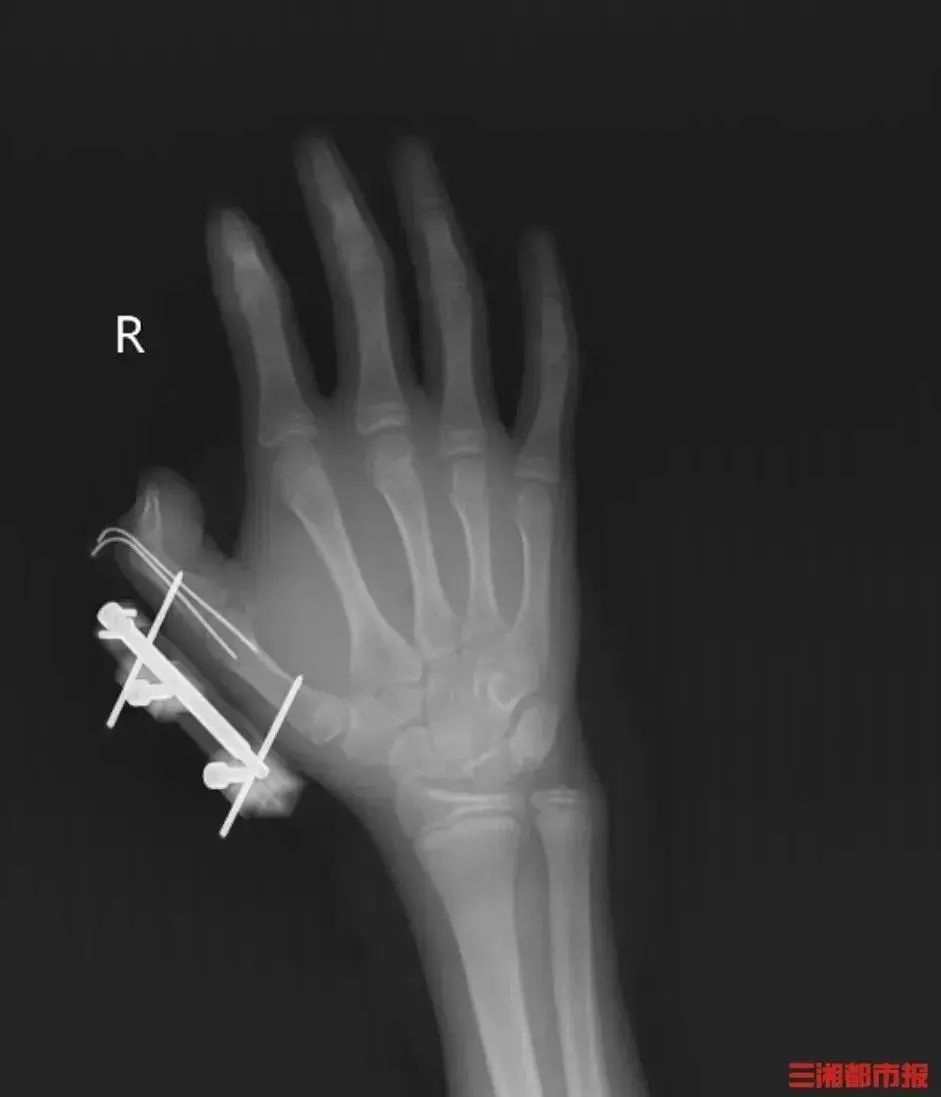

看看您的冰箱是否可用!这个14岁的男孩差点摔断

这个14岁男孩的手指被深深地吹来,看到他的骨头 很快,一个来自亨南(Hunan)的14岁男孩(假名)发现了干冰来冷却父亲的在线购物盒,因此他将其删除并以玩具为玩,将其夹在手中,并反复摇动它。 突然,密封袋中的干冰爆炸了,血液流入魏维的右手。大约10厘米的伤口被撕开以张开他的拇指嘴,深渊可见,肌肉组织受损和暴露,伴随着拇指的骨折和关节的脱位,整个拇指完全不见了。 当他看到这一点时,他的家人迅速将他带到当地医院进行绷带,然后敦促湖南省人民医院和显微外科手术。在治疗后,维维(Vivi)的拇指被保留下来,但仍然需要长期的康复训练来减慢手的精细运动功能。 weiwei 干冰不是“冰” 漏洞的力量sion与烟花 干冰,也称为二氧化碳,通常是一种无毒性和无味的白色固体,具有多种形状。在室温和压力下,干冰可以直接升华为二氧化碳气体。当升华时,体积会延伸800至1000次。加入热水后,它可以迅速加速并产生大量的烟气。 湖南省人民医院手和显微外科部主任陈江介绍,如果将干冰放在密封的袋子里摇晃并摇动,而气体将继续增加,那么该袋将爆炸,如果不能在压力下爆炸。爆炸产生的权力是普通烟花的很多次,而立即死亡则无法被估计。 干冰的使用无效 可能是致命的风险 爆炸 在密闭容器中使用干冰:干冰很容易在室温下转换为二氧化碳,导致气密容器的压力增加,这是一个D超过公差极限后发生爆炸。 △图像来源:广东的火灾保护 将干冰放在冰箱中:干冰温度约为-78.5℃,而冰箱冰箱温度在-4℃和-24℃之间。因此,将干冰放在冰箱中后,它将继续升华并产生大量二氧化碳气体,从而在冰箱内发生过多的压力和撞击。 △图像来源:广东的火灾保护 窒息 通过升华干冰产生的二氧化碳气体会给人类带来呼吸困难。如果它位于相对封闭的空间中,可能会在短时间内造成困难和危险的生活。 冻疮 干冰是固体二氧化碳,温度低于-78.5℃。直接皮肤接触立即消除热量,这很容易引起霜冻,甚至是皮肤的坏死,在严重的情况下,它会损害肌肉和骨骼。 收到了冷链包装 如何安全处理干冰? 不要让您的孩子触摸 父母应该将干冰放在他们的孩子没有因为“烟雾”而对孩子玩耍的好奇,并且显然告诉他们的孩子Na Dry Ice不是玩具。 否认狭窄的空间 请勿将干冰存储在密封的容器中,例如矿泉水瓶或冰箱中;干冰应放在整洁的地方。 请勿将干冰存储在汽车之类的狭窄空间中。 互动时佩戴保护 不要与干冰直接互动。为了防止霜冻,请使用防冻剂或夹子手套获得干冰。 受伤后立即寻求医疗 当人皮与干冰接触时,会发生露水加热的压缩性周围炎和冻伤乳霜进行治疗。如果霜冻是严重的,请按时寻求医疗。 当干冰吹伤时,请立即寻找医疗以防止治疗延迟。 资料来源:国家紧急情况播送 IPASA是提醒↓Agan